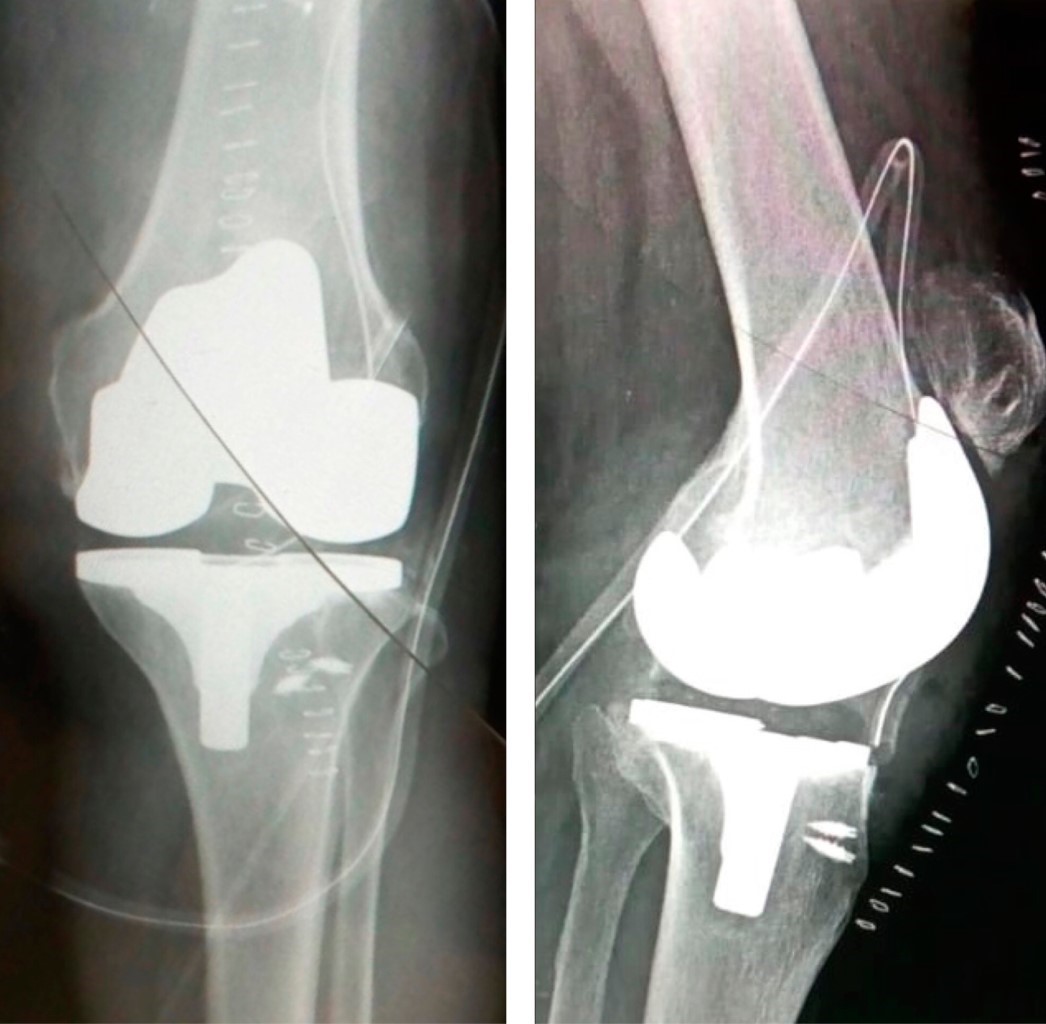

Se solicitó radiografía simple, encontrando en la proyección lateral fragmento avulsionado de tuberosidad tibial con migración proximal de rótula más cambios osteodegenerativos femorotibiales grado IV. En proyección anteroposterior se observa compartimento lateral con artrosis femorotibial grado IV (Figura 1). Se solicita eje mecánico encontrando deformidad en genu varo de 10o (Figura 2).

El segundo tiempo quirúrgico se realiza 16 meses después con el objetivo de resolver el daño articular, una vez ya resuelto el problema del mecanismo extensor, se colocó una prótesis primaria Smith & Nephew ANTHEM™; no se colocó el componente rotuliano debido al trayecto del túnel por donde pasan los tendones de la pata de ganso (Figura 4).

Figura 1

Figura 3

Figura 4